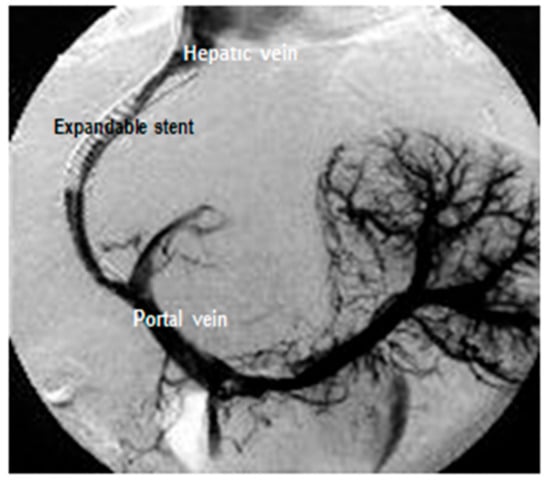

- Radiologic treatments include TIPS (transjugular intrahepatic portosystemic shunt) and BRTO (balloon retrograde transvenous obliteration).